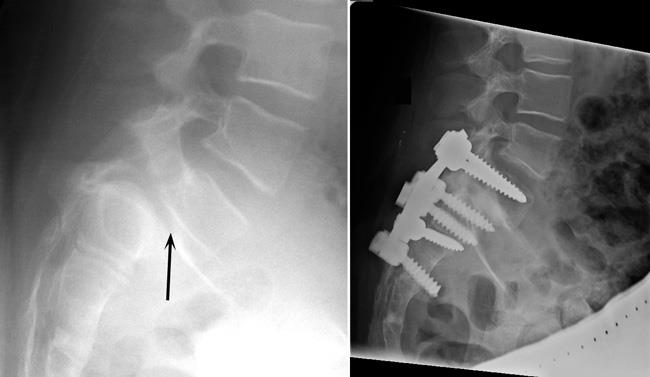

SPONDYLOLISTHESIS CORRECTION

Treatment for spondylolisthesis is similar to treatments for other causes of mechanical and compressive back pain. Surgery is necessary only if conservative treatments fail to keep a patient’s pain at a tolerable level. Surgical treatment for spondylolisthesis must address the presence of mechanical and compressive symptoms. Nerve pressure may require surgical decompression, called decompressive laminectomy of the lumbar spine. Patients needing surgery for spinal instability due to spondylolisthesis will typically require lumbar fusion.